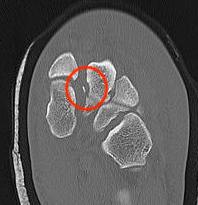

CT

Fleck sign

Fleck sign with inter-cuneiform widening